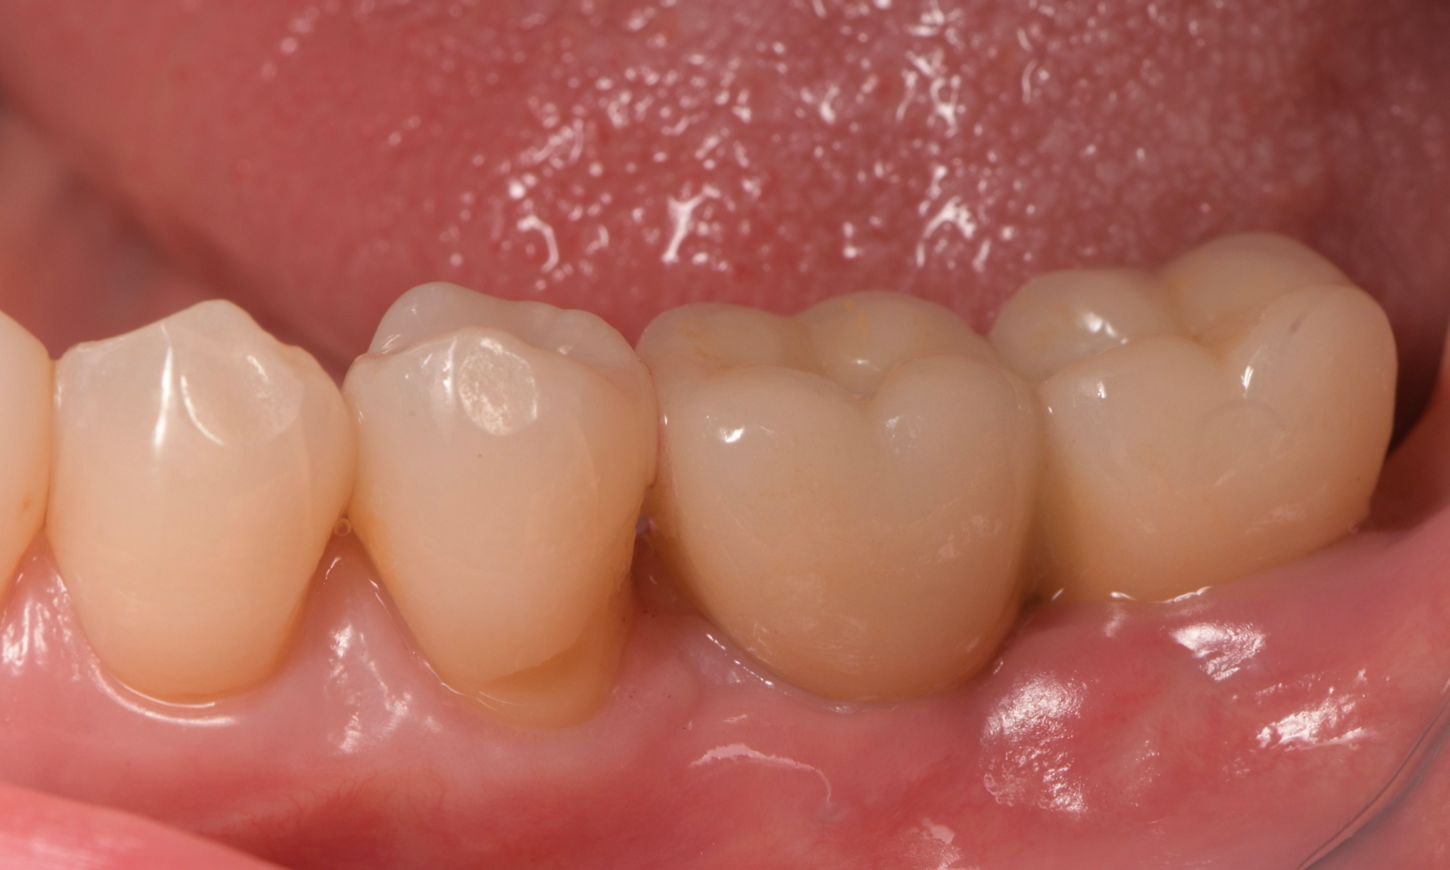

The gingiva was evaluated before the placement of the final prosthetics (Fig. 19). A fully polished zirconia prosthetic was then carefully fabricated and inserted, and torqued to 35 Ncm (Figs. 20,21) and the subsequent x-ray revealed satisfactory results (Fig. 22).

Fig. 19

Fig. 21

Fig. 20

Fig. 22